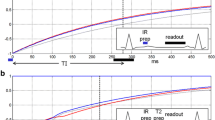

T1 quantification

T1 quantification was performed with a Modified Look-Locker Inversion-recovery (MOLLI) sequence [11], acquired in a mid-ventricular short-axis slice before and 1, 3, 5, 9, 20 min after contrast administration. Multiple post-contrast measurements were performed to show the optimal time point of image acquisition after contrast administration. Imaging parameters were: non-selective inversion pulse, steady-state free precession single-shot read out in mid-diastole, field of view 223 × 320 mm, matrix 174 × 192, slice thickness 8 mm, TE 1.08 ms, FA 35°, bandwidth 1002Hz/Px, minimum inversion time of 100 ms, maximum inversion time of 3600 ms.

T1 mapping

For technical reasons we were able to perform a pairwise analysis in only six patients of group A. Interestingly, in this subgroup we found no significant differences between both contrast media regarding T1 times of the different tissues at different time- points after contrast administration (Table 5).

The drop-out rate was high due to two main-aspects: I) The applied sequence was a first generation one as described in the method section. II) The most frequent limitation was the registration failure of the raw images especially in regions of wall thinning respectively the infarct area.

SNR- and CNR of LGE images are influenced by inversion time. Its adjustment is operator-dependent. T1-mapping was expected to add information on contrast-media timing, but for technical reasons we were only able to complete a pairwise T1 analysis in six patients of group A. Larger studies preferably with mapping techniques are needed to confirm our results.